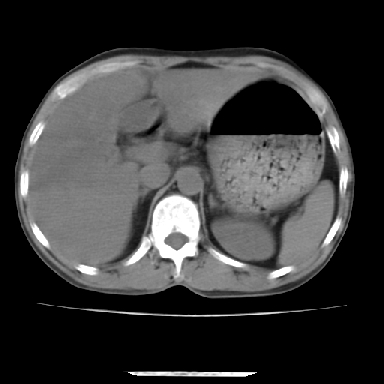

标题: CT7372:脂肪肝?外伤? [打印本页]

标题: CT7372:脂肪肝?外伤?

m 45 车祸,硬膜下血肿

窗宽太宽,调低点就好了,应该是不均质脂肪肝表现,请结合临床,单纯肝挫伤  其内无出血灶很少见,必要时做mri检查

窗宽太大,对比度太差了。局限性脂肪肝也有可能,但是亦不排除外伤性改变,增强扫描应该也还可以鉴别的。

肝内未见出血灶,但不能除外外伤性肝损伤,所示层面应考虑弥漫性脂肪肝.请结合临床必要时做mir检查

肋骨无骨折,腹腔未见游离液体,所以不均匀脂肪肝首先考虑,但如果病人情况允许还是做个增强检查放心

考虑不均匀性脂肪肝,肝包膜下光整,肋骨无异常,无腹水征,不支持肝挫伤。